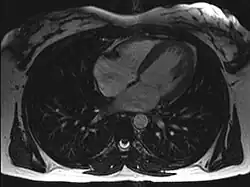

Magnetic resonance imaging visualizes the heart by detecting hydrogen atoms using superconducting magnets, particularly those attached to water and fat molecules.[9] These hydrogen atoms possess a property known as nuclear spin. Although the direction of this spin is usually random, the spin can be aligned using a powerful magnetic field.[9] Faint electromagnetic signals are emitted by these hydrogen atoms when their alignment is temporarily disturbed which can be detected and used to create an image of the heart.[10]

Cardiovascular magnetic resonance (MR) technology is able to measure the size, shape, function, and tissue characteristics of the heart in a single session.[11] It is also commonly used to determine ventricular function and for the evaluation of structural heart disease.[12] It is more reproducible than echocardiography with less inter-observer variability, allowing for more precise reference ranges to better distinguish health from disease.[11] Additionally, MR lacks ionizing radiation and does not have any known long-term effects, making it safe for repeated imaging.[13]

Additional benefits from cardiac MRI include the ability to detect scar within the heart using late gadolinium enhancement, and identify other abnormalities of the heart muscle itself such as infiltration with iron or amyloid protein.[11] Disadvantages of MRI include lengthy protocols and the potential for claustrophobia. Furthermore, an MRI scan cannot be performed in some people who have metallic implants such as some types of pacemakers, defibrillators, although many modern pacemakers are safe for use within an MRI scanner.[14] Other metal structures such as artificial valves and coronary stents are generally not problematic. However, MR is less widely available and may be more difficult for patients to tolerate than other noninvasive modalities, requiring physician monitoring for complex cases.[13]